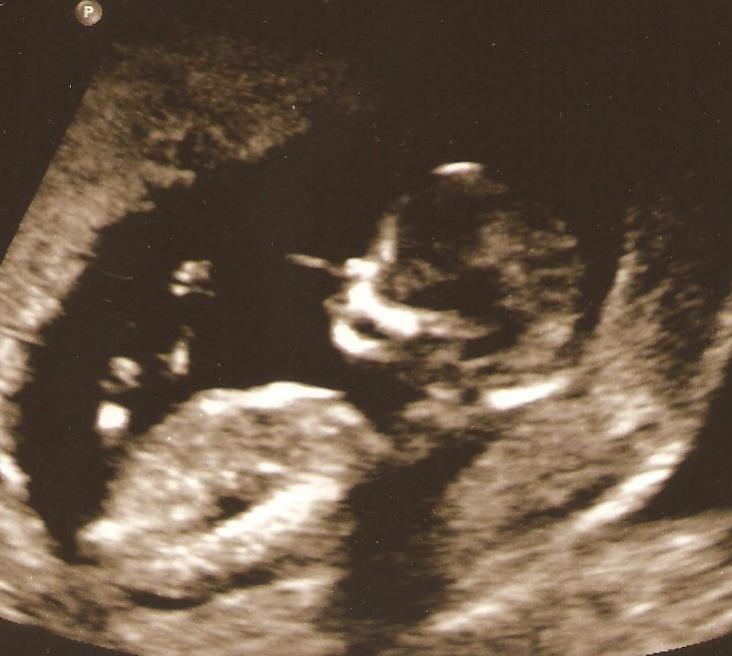

Yikes, haven't posted on here in awhile! Gave up on swaying for a girl in June since this is my first and decided to see what #1 would be before swaying for the next. I got pregnant at the end of July and just had my 13 week NT scan. What do you all think?!?! I'm thinking girl, but not sure. Any guesses would be appreciated!

Attachment 654